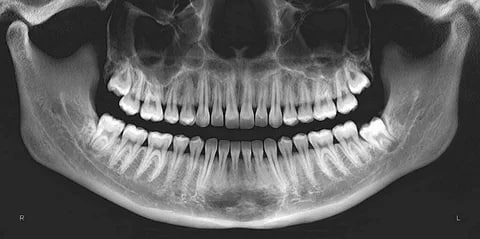

Лечение зубов обойдётся россиянам в два раза дороже в 2026 году, предупреждают эксперты. Основные причины — подорожание материалов, логистики, повышение НДС до 22% и увеличение стоимости аренды помещений.